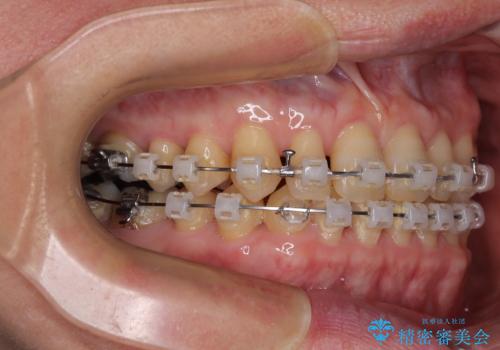

- 矯正装置

- クリアブラケット

手前に傾斜している奥歯をワイヤー装置で立ち上がらせ、咬み合わせの高さを挙上することで突き上げを解消し、空隙歯列を改善していくこととしました。

ディープバイトが改善され、睡眠時の食いしばりも緩和され、顎への負担が軽減されました。